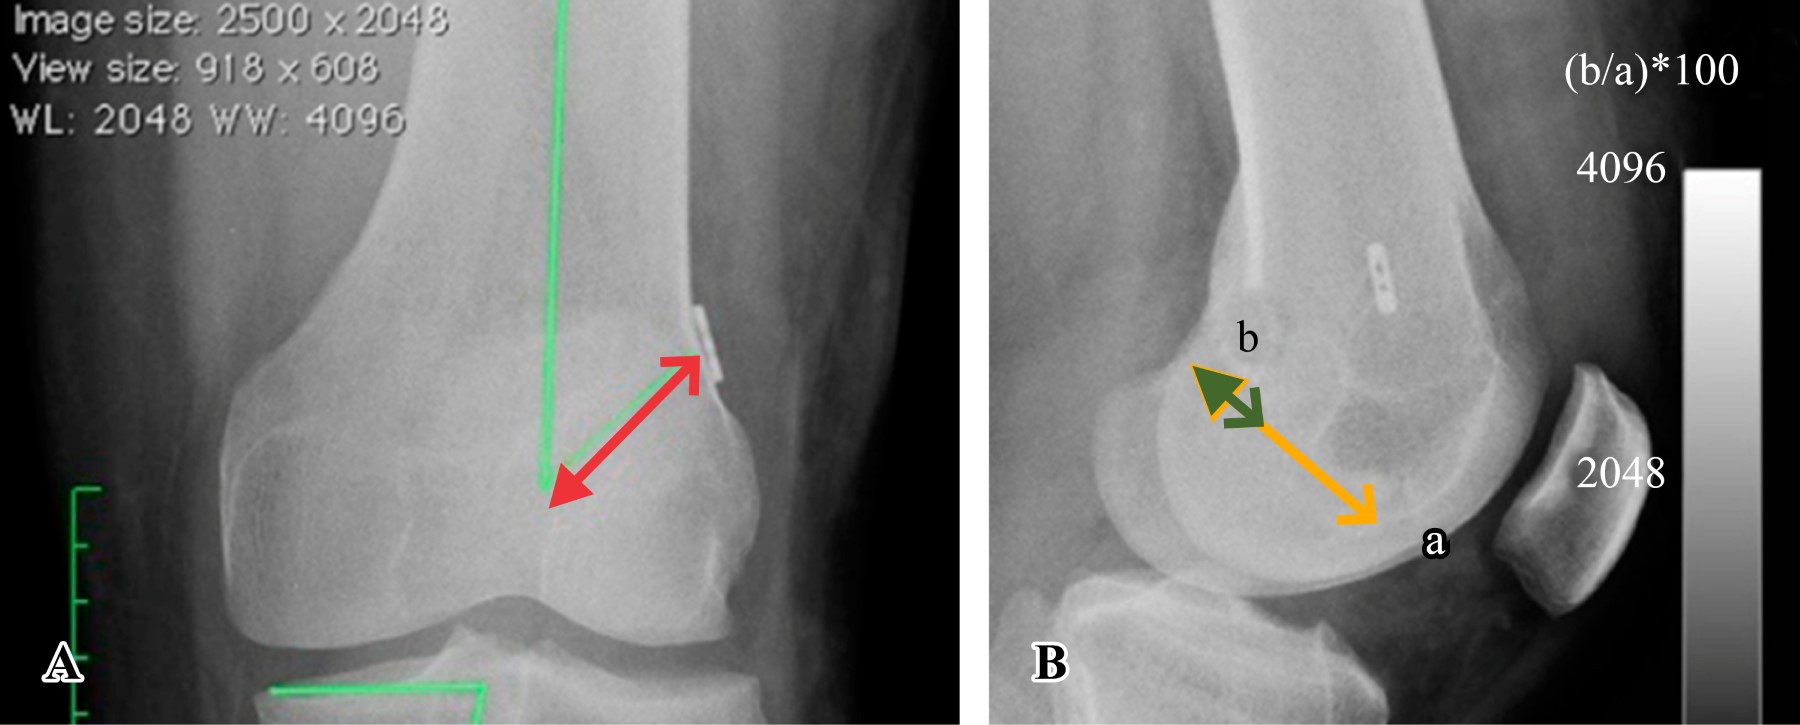

Tibial tunnel position. Tibial tunnel positioning was calculated by Acl Tunnel Position X Ray  Tunnel positioning assessment is a major issue after anterior cruciate ligament (acl) reconstruction surgery. Femoral and tibial tunnels are crucial for graft stability and good clinical outcomes and should be evaluated and documented in every patient who. Femoral tunnel positioning must be assessed in both the sagittal and coronal planes. A comprehensive systematic review was performed using medline and pubmed. Acl Tunnel Position X Ray.

A B Measurement Of The Femoral And Tibial Tunnel In L vrogue.co Acl Tunnel Position X Ray  A comprehensive systematic review was performed using medline and pubmed searches to identify radiological methods used. Patients with complications of acl. We create orthogonal coronal and sagittal plane reformat images and two volume. Femoral tunnel positioning must be assessed in both the sagittal and coronal planes. Femoral and tibial tunnels are crucial for graft stability and good clinical outcomes and. Acl Tunnel Position X Ray.

Lateral radiographic knee view showing the anterior cruciate ligament Acl Tunnel Position X Ray  Patients with complications of acl. Femoral tunnel positioning must be assessed in both the sagittal and coronal planes. We create orthogonal coronal and sagittal plane reformat images and two volume. A comprehensive systematic review was performed using medline and pubmed searches to identify radiological methods used. Tunnel positioning assessment is a major issue after anterior cruciate ligament (acl) reconstruction surgery.. Acl Tunnel Position X Ray.